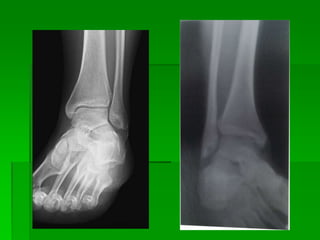

ARTICULACION DE TOBILLO

Tobillo de frente

Estructuras mostradas:

 Extremos proximales de los

metatarsianos.

 Extremos distales de la tibia y el peroné.

 La porción proximal del astrágalo.

 El maléolo interno.

 El hueso cuboides